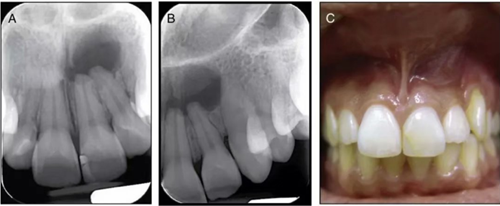

檢查:21牙冠顏色略有變化,近中充填體涉及切緣和近中面,22無齲壞和充填體,21.22冷熱診,電活力測試陰性,叩診無不適,22根尖區(qū)域可見局限性的腫脹,觸診無波動性,質(zhì)地較硬;

X線片:21折裂線未及髓腔,21、22根尖區(qū)大范圍低密度投射影像;

圖2. 術(shù)前X線片及口內(nèi)照。